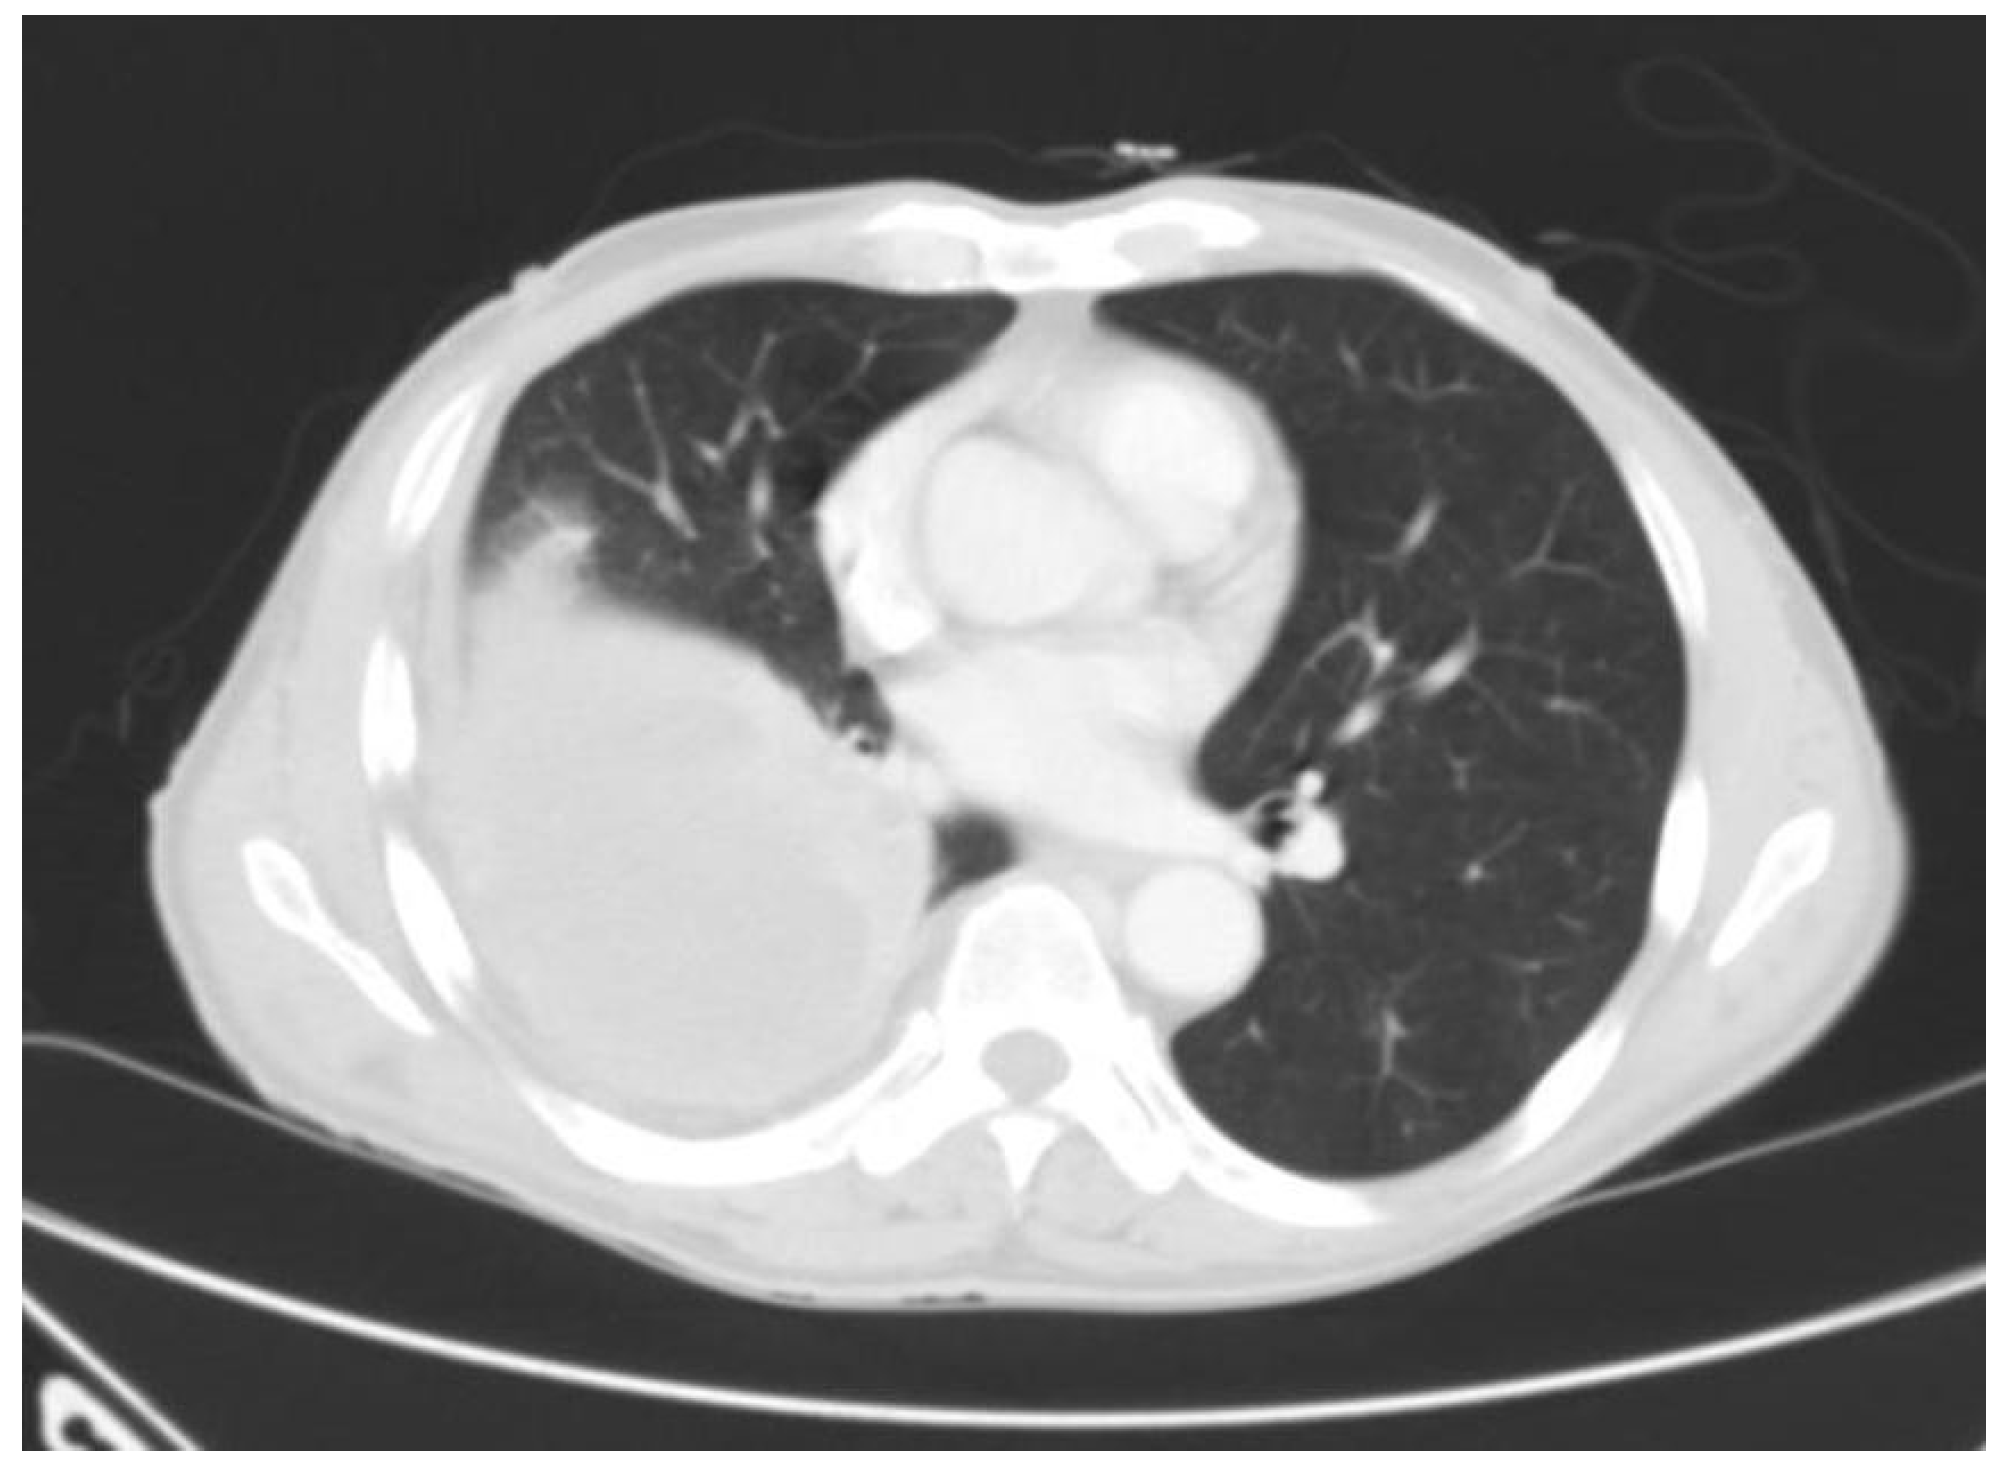

Tuberculous Empyema Presenting as a Persistent Chest Wall Mass: Case Report

Madeo, J.; Patel, R.; Gebre, W.; Ahmed, S. Tuberculous Empyema Presenting as a Persistent Chest Wall Mass: Case Report. GERMS 2013, 3, 21-25. https://doi.org/10.11599/germs.2013.1033